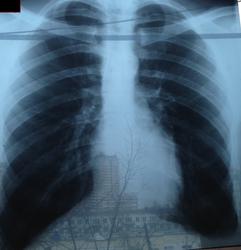

Сделал рентгенографию. Лечу бронхит муколитическим (ацц), пью много воды. Врач с которым консультировался сказал что противовирусные принимать поздно, а антибиотики пока не нужно, т.к. состояние более менее. Направил в диспансер проверить на туберкулез.

Можно ли что-то сказать по снимкам?

На фоне пейзажа на рентгенограмме трудно что-либо разглядеть, но на мой взгляд нормальные легкие. Рентгенолог много написала, видимо с фантазией все в порядке

Патологических изменений не определяю.